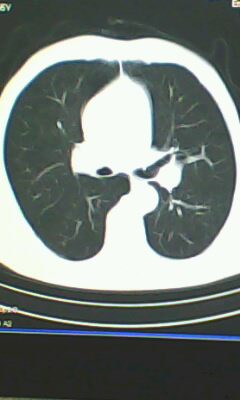

标题: CT26182:男 胸憋 无其它异常症状

胰尾部占位?

未见明显异常。“胰尾占位”为肠管

口服造影剂是必须的

弥漫性肺气肿 但内胆管轻度扩张